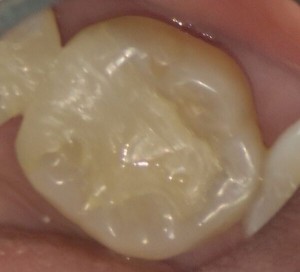

以前から口を開けたときの歯の色が気になっていたとのことで、銀歯を白くしたいとのご希望で来院されました。

銀歯の隣の歯も黒く、虫歯になっていたため、エックス線写真を撮影しました。

治療前の歯は以下のような状態でした。